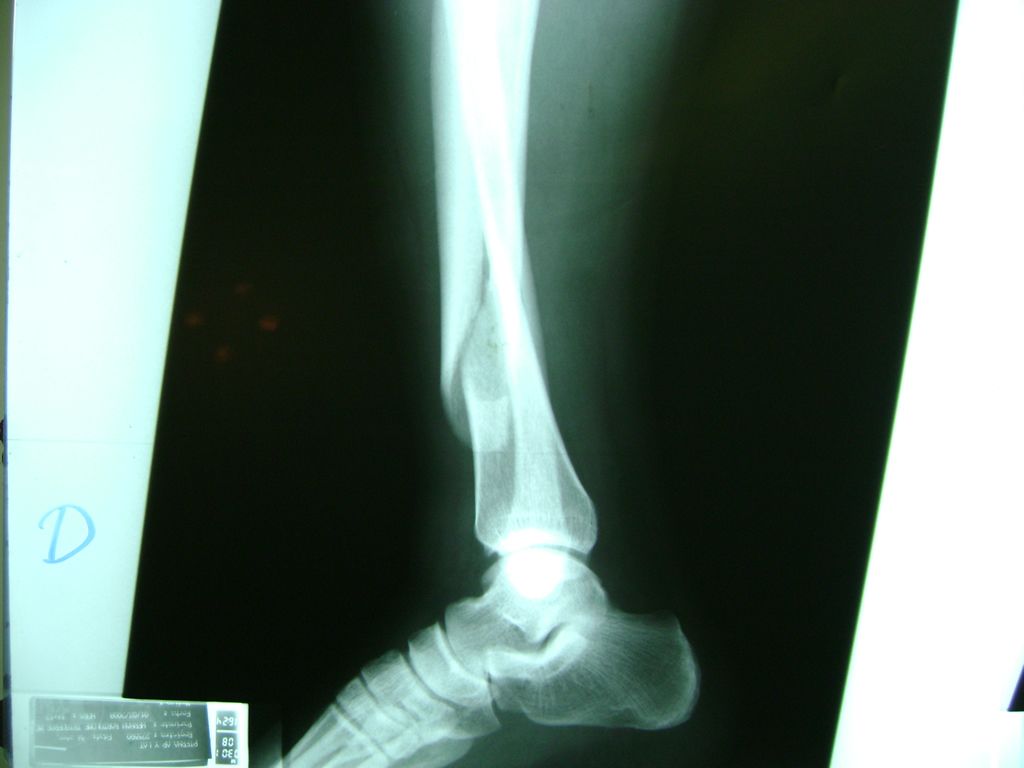

Cirugias en El Salvador - Perone y Tibia

Aunque cada uno de estos huesos puede fracturarse por separado, normalmente la rotura es una lesión que se produce de forma conjunta

La mayor parte de las roturas implican a la parte proximal del hueso (parte del hueso próximo a la rodilla) o a la parte distal (parte del hueso cerca del tobillo).

Debido a la fina cobertura de piel que recubre la tibia y el peroné, las fracturas generalmente son abiertas, es decir, el hueso roto rasga la piel, atravesándola. Las fracturas de tibia y peroné generalmente se producen por un fuerte impacto o torsión.